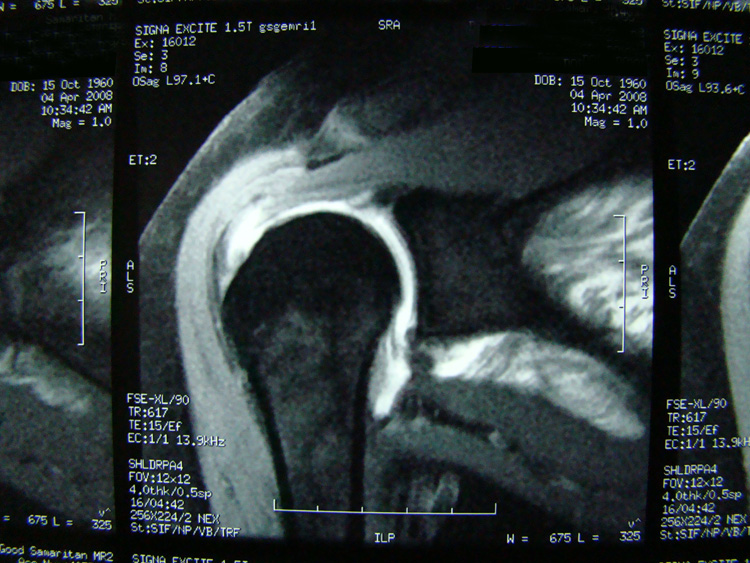

This patient presented with shoulder pain that interfered with work and exercise. The visible fluid-filled cysts on the “Before" MRIs are from chronically injured rotator cuff tendon roots.

The patient underwent treatments of a highly specialized fine-needling technique pioneered by Dr. Tallman.The follow-up MRI was done 2 months after his 6th treatment. He was released with a pain-free, full range of motion with unrestricted activities.